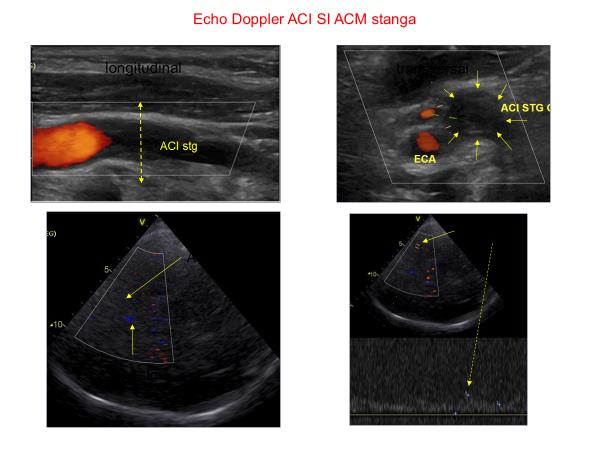

Ecografia Doppler cervicala si transcraniana codata color este o tehnica imagistica utilizata in Policlinica The Light de asist. univ. dr. Mirabela Manea, medic specialist Neurologie, pentru evaluarea depunerilor de placi de colesterol (ateromatoza), a stenozelor/ocluziilor, a disectiilor arteriale, uneori a malformațiilor vasculare intracerebrale sau a anevrismelor intracerebrale de mari dimensiuni. Permite vizualizarea arterelor carotide, arterelor vertebrale si arterelor subclavii de la nivelul gatului, precum si a arterelor cerebrale prin craniul intact.

Pentru a putea evalua efectele secundare asupra circulatiei cerebrale ale unei stenoze/ocluzii arteriale cervicale intotdeauna este obligatorie efectuarea ecografiei Doppler cervicale inaintea celei transcraniene. Aceste examinari necesita experienta in patologia cerebrovasculara a medicului neurolog care efectueaza examinarea pentru interpretarea corecta a datelor obtinute si pentru a putea stabili un tratament adecvat.